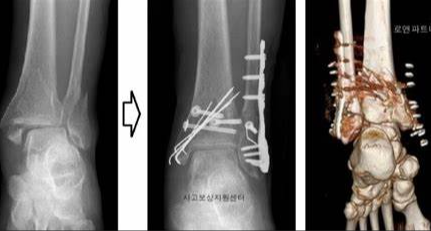

3. 골절

발목 골절은 발목 뼈 중 하나 이상이 부러진 경우를 말합니다. 이는 추락, 사고 또는 스포츠 부상과 같은 다양한 이유로 발생할 수 있습니다.

치료 방법 :

- 캐스트, 스플린트 또는 브레이스로 고정합니다.

- 일부 경우에는 부러진 뼈를 다시 정렬하고 안정화하기 위해 수술이 필요할 수 있습니다.

- 힘과 기동성을 되찾기 위한 물리 치료가 필요할 수 있습니다.